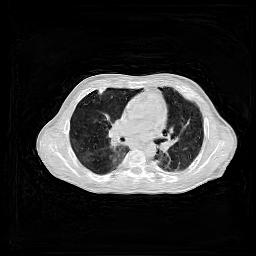

IV-C Few-View CT Reconstruction

In this section, the reconstruction performance of our proposed framework under few-view conditions will be tested. For the parallel and fan beam geometry, the number of views increases from to , uniformly distributing from to and to respectively. Such settings provide a complete benchmark of reconstruction performance, ranging from extremely sparse to relatively complete, full-view CT reconstruction. The experiment results are shown in Fig.5. Additionally, the ground truth, few-view ( views), and full-view ( views) CT reconstruction results of different methods are shown in the first and third rows of Fig.7 (parallel-beam, LIDC-IDRI dataset), and Fig.8 (fan-beam, LIDC-IDRI dataset).

(a) Ground Truth

43.87dB/0.96

(b) ASD-POCS

47.96dB/0.97

(c) RBP-DIP

34.46dB/0.84

(d) DIP

26.63dB/0.93

(e) MED50

29.03dB/0.95

(f) RED-CNN